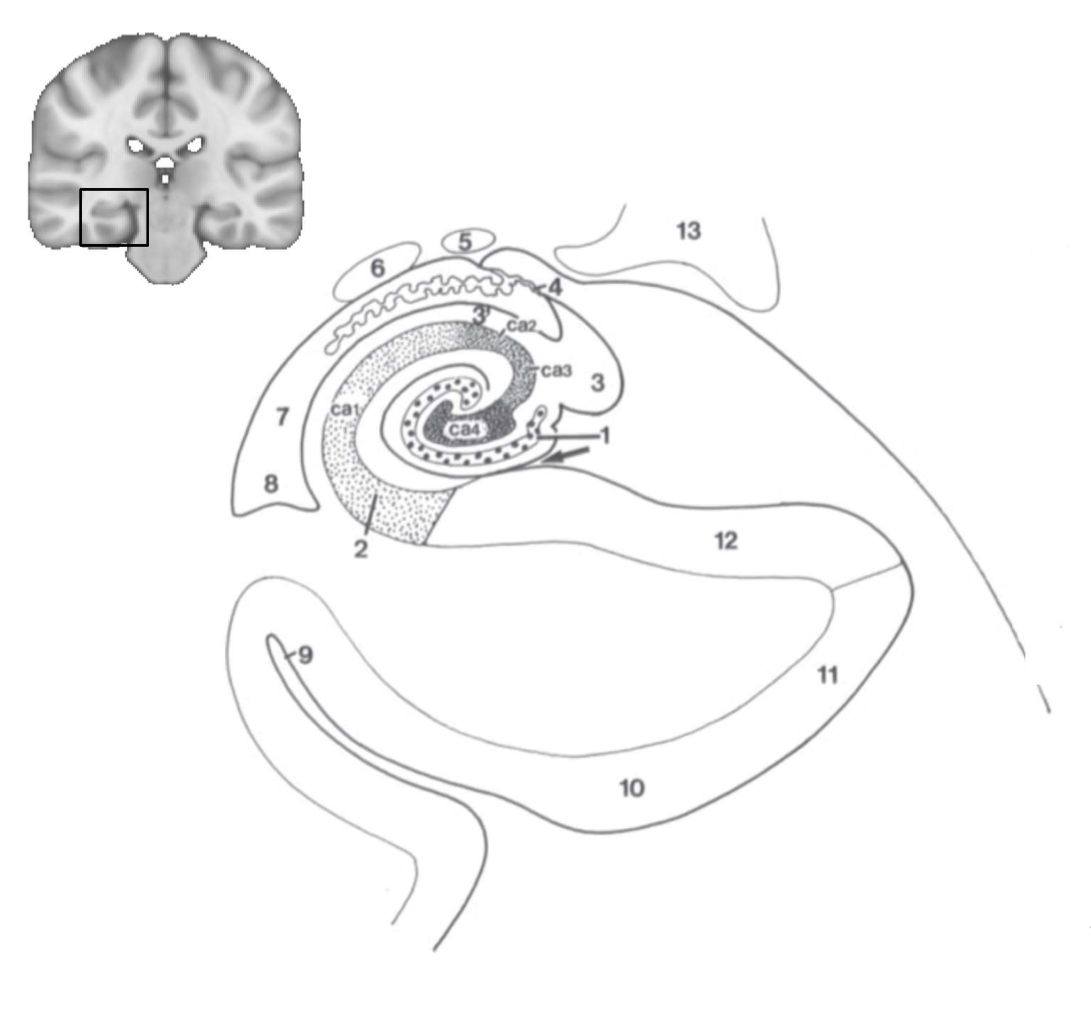

What structure is this?

hippocampus

What is 1?

hippocampus

What is 2?

rhinal sulcus

What is 3?

lateral ventricle

What is 4?

thalamus

What is 5?

entorhinal cortex

What is 6?

perirhinal cortex

What is 7?

parahippocampal cortex

What is 1?

gyrus dentatus

What is 2?

cornu ammonis

What is 3?

fimbria

What is 3’?

alveus

What is the arrow pointing to?

happicampal sulcus

What is ca1, ca2, ca3 and ca4?

fields of cornu ammonis

What is 4?

tela choroidea

What is 5?

stria terminalis

What is 6?

tail of caudate nucleus

What is 7?

temporal horn of lateral ventricle

What is 8?

collateral eminence

What is 9?

collateral sulcus

What is 10?

parahippocampal

What is 11?

entorhinal area

What is 12?

subiculum

What is 13?

lateral geniculate body